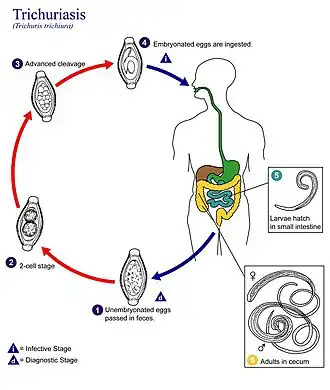

Власоглав имеет широкий задний и нитевидно утончённый передний конец тела, что придаёт ему сходство с кнутом. Взрослые гельминты паразитируют в слепой и ободочной кишке, глубоко внедрившись в слизистую передними концами тела. Тысячи яиц, ежедневно откладываемые самкой, выходят с калом наружу и дозревают в почве. После проглатывания человеком яиц из них в двенадцатиперстной кишке вылупляются личинки, которые созревают и затем мигрируют в толстую кишку. Цикл развития паразита занимает около 3 мес. Срок жизни взрослых гельминтов составляет несколько лет.